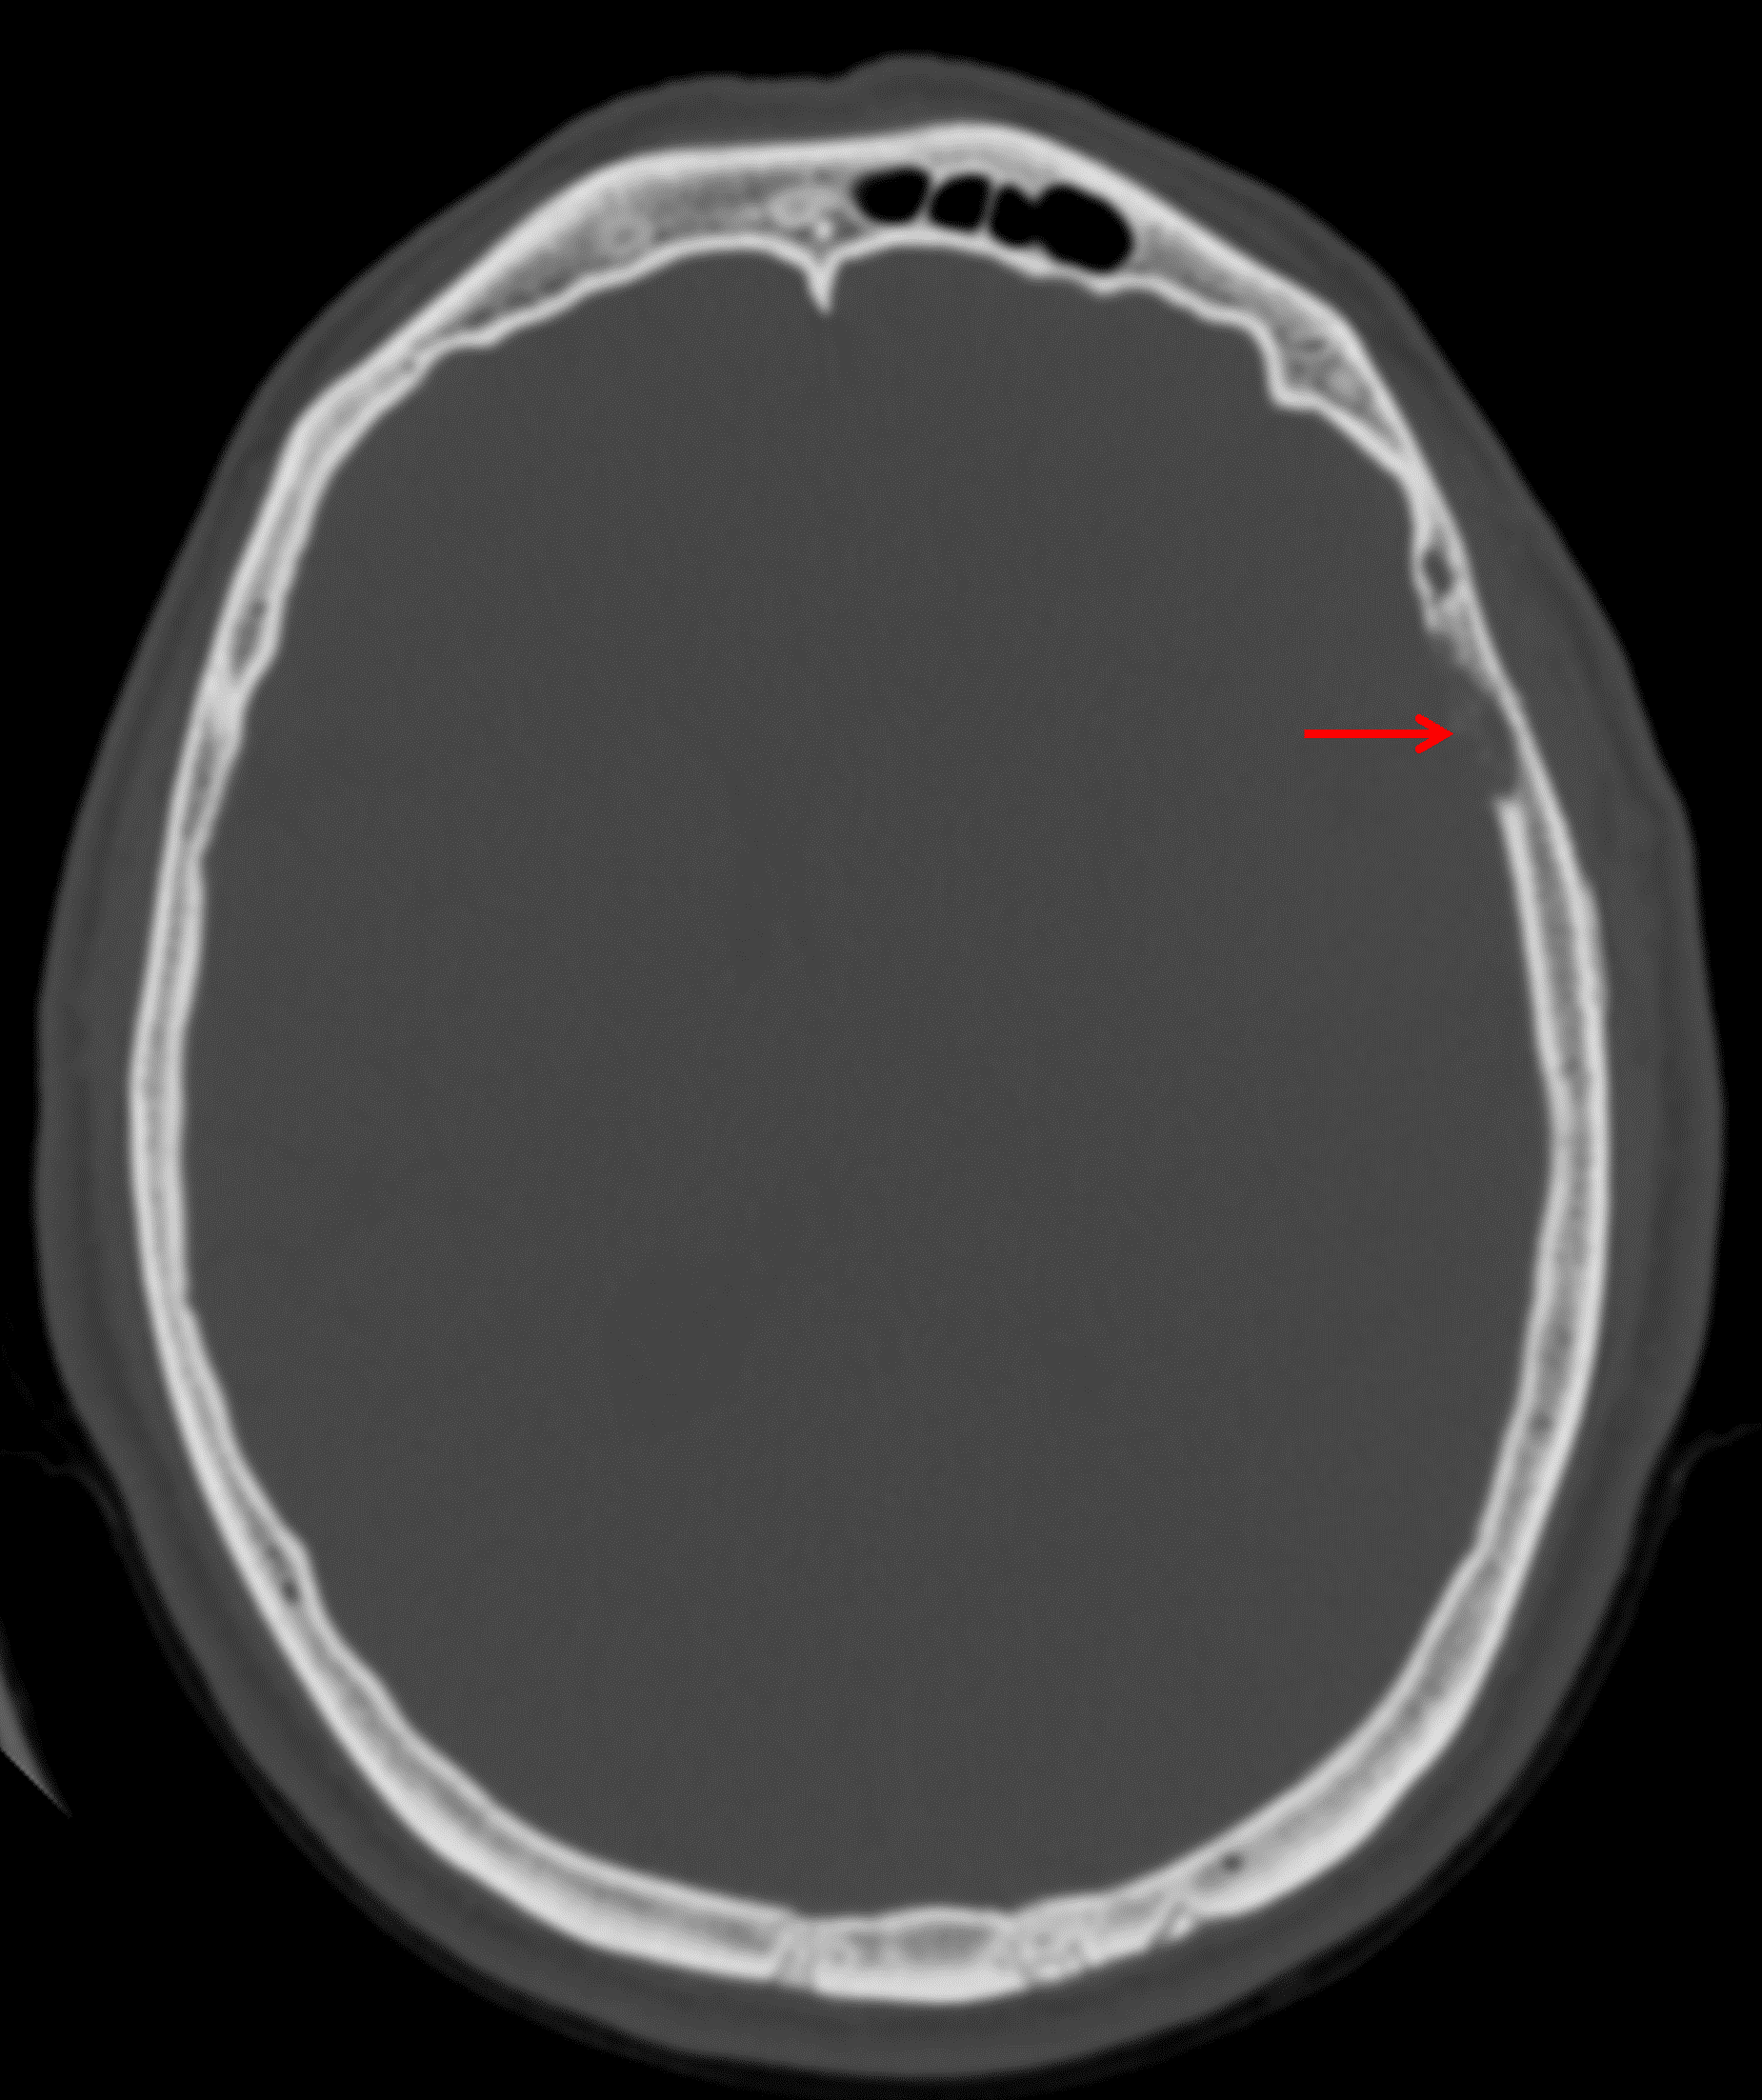

CT

- Lytic changes involving the inner table of the overlying calvarium

Inner table calvarial erosion overlying the mass (red arrow).